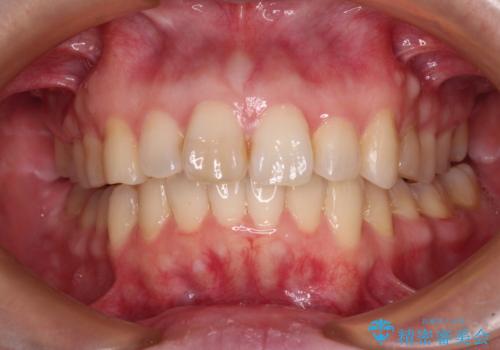

奥歯の咬み合わせを見ると、上顎が下顎に対して相対的に前方にありました。

口元の閉じにくさを改善するためには、上顎臼歯を後方に移動させた咬み合わせにする必要があります。

インビザライン単体で改善することも可能ですが、達成する可能性が高くないため、カリエールディスタライザーという補助装置を併用して、より確実性を上げることとしました。

奥歯の咬み合わせを改善しながら、並行してインビザラインで歯列を整えることとしました。